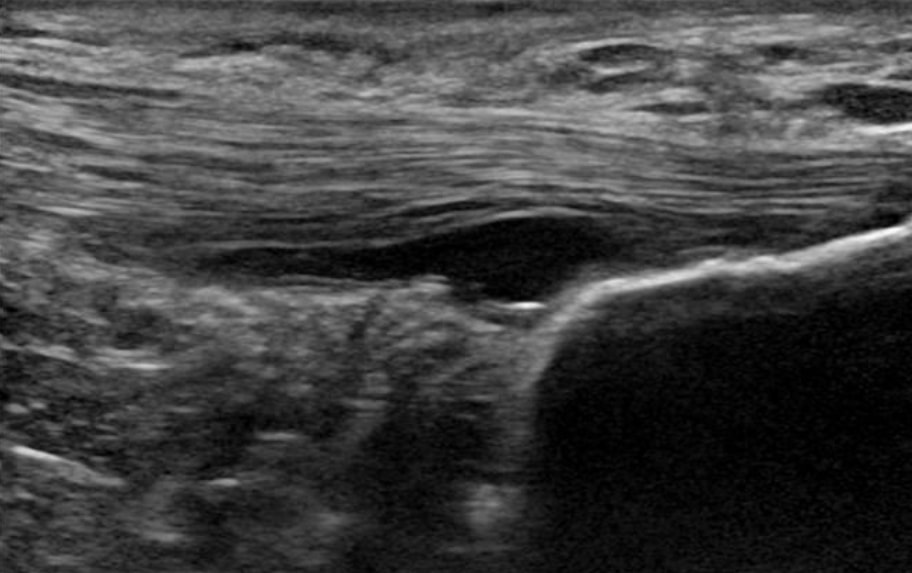

6. Gân bệnh lý có cấu trúc tốt hơn gân bình thường ( Docking và cộng sự). 2015 ). Điều này có nghĩa là chúng ta có thể tải các gân này vì chúng ta có nhiều mô tốt. Bất kỳ liệu pháp nào cho bệnh lý gân đều không cần thiết, vì dù sao chúng ta cũng không thể thay đổi cấu trúc của phần bệnh lý. Vì lý do này, Docking và các đồng nghiệp đã đưa ra câu trích dẫn “Hãy điều trị phần bánh rán, chứ không phải phần lỗ” – nói cách khác, hãy tập trung vào phần cấu trúc khỏe mạnh chứ không phải phần bệnh lý.

Gân bệnh lý có cấu trúc tốt hơn gân bình thường (Docking và cộng sự. 2015)